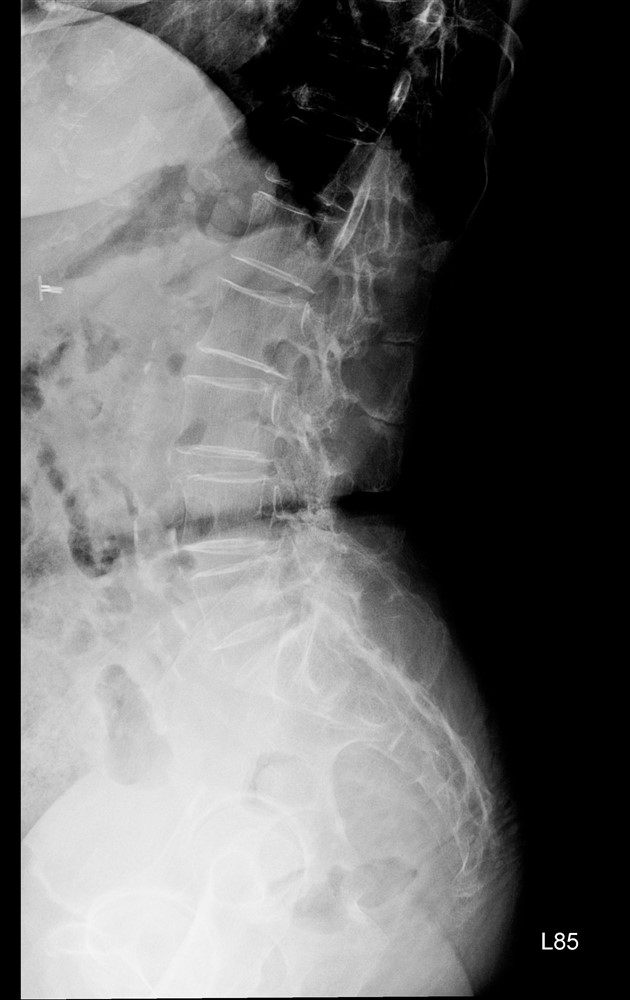

八十五歲的林女士在十多年前與七、八年前曾分別接受兩次腰椎手術,近來卻出現劇烈腰痛,翻身時疼痛指數高達八分,甚至難以入睡。影像檢查發現,她的腰椎第一與第二節出現嚴重狹窄,需要再次手術。

神經醫學中心團隊採用「截釘翻修技術」,處理高齡與多次手術史的複雜個案。「截釘翻修技術」的概念並非完全拆除舊有植入物,而是在原有固定系統仍可利用的情況下,截短或延伸固定桿,再重新連接新的固定結構,如此可以避免大範圍拆除植體與肌肉剝離。

林女士的手術過程順利,術後十天疼痛感即明顯緩解。兩個月後,她已能每天步行半小時,生活品質大幅改善。對她而言,最大的改變是終於能夠「一覺睡到天亮」。

神經醫學中心統計顯示,近兩年共有五十多名患者接受截釘翻修手術,平均出血量比傳統延長固定手術少約一百五十毫升。對於高齡或慢性病患者而言,出血量減少意味著感染與心血管負擔也隨之降低。

術前

術後

林女士術前與術後的影像檢查結果。